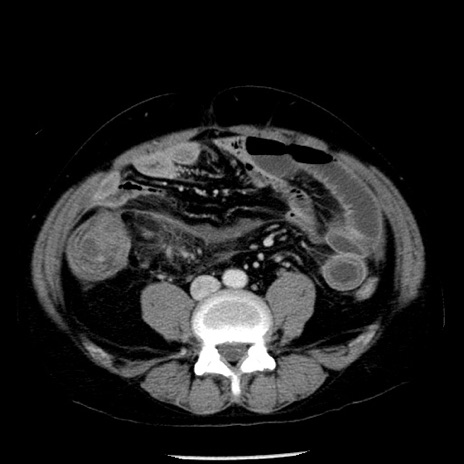

症例29(横断像)

【症例】40歳代男性

【現病歴】2日前から胃痛あり。徐々に周期的な激痛に変化した。本日になっても激痛があるため受診。

【身体所見】意識清明、BT 38-39℃台あり、腹部:膨満、やや硬、右下腹部に圧痛あり。

【データ】WBC 8500、CRP 23.26